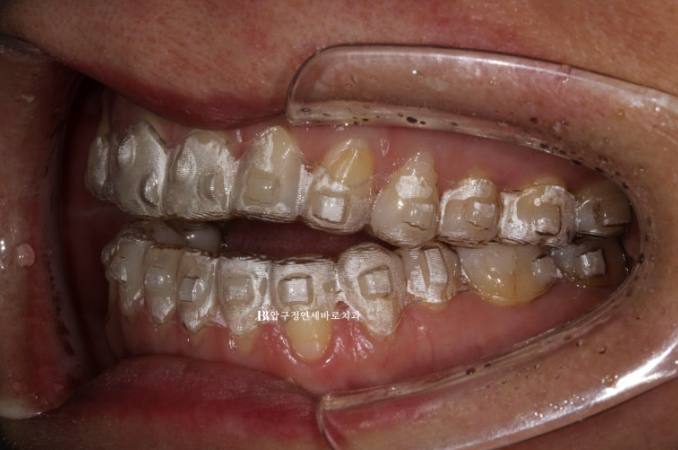

올해 5월 개방교합 때문에 찾아오신 50대 환자분입니다.

위 어금니를 뼛속으로 밀어올리는 함입교정이 필요함을 설명드렸습니다.

23.05

첫번째 작은어금니까지 8개 치아는 떠있고 두번째 작은어금니부터 큰어금니까지 3개씩 닿아있는 상태입니다.

이런 상태에서는 닿고있는 위 어금니 3개씩 총 6개 치아를 함입시키는 치료계획으로 진행합니다.

초기부터 입천장에 미니스크류를 심었습니다.